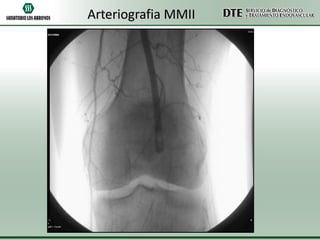

Arteriografía MMII

Arteriografia MMII

•Conclusiones:

•Oclusión completa de arteria poplítea izquierda

•Oclusión de arteria tibial posterior derecha

•Conclusiones: •Oclusión completa dearteria poplítea izquierda •Oclusión de arteria tibial posterior derecha